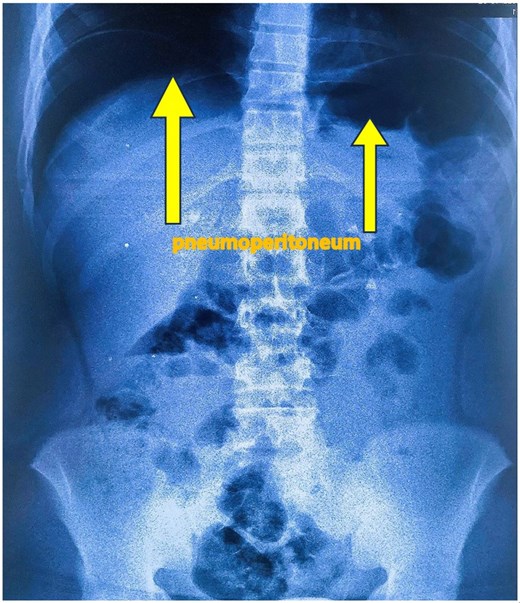

An upright abdominal X-ray revealed massive bilateral pneumoperitoneum (Fig. 2), contrasting with the subtle abdominal signs. This clinical-radiological mismatch prompted an abdominopelvic CT scan, which confirmed the presence of abundant free intraperitoneal air, without clearly identifying the perforation site (Fig. 3).

Standing abdominal plain X-ray showing large bilateral pneumoperitoneum.